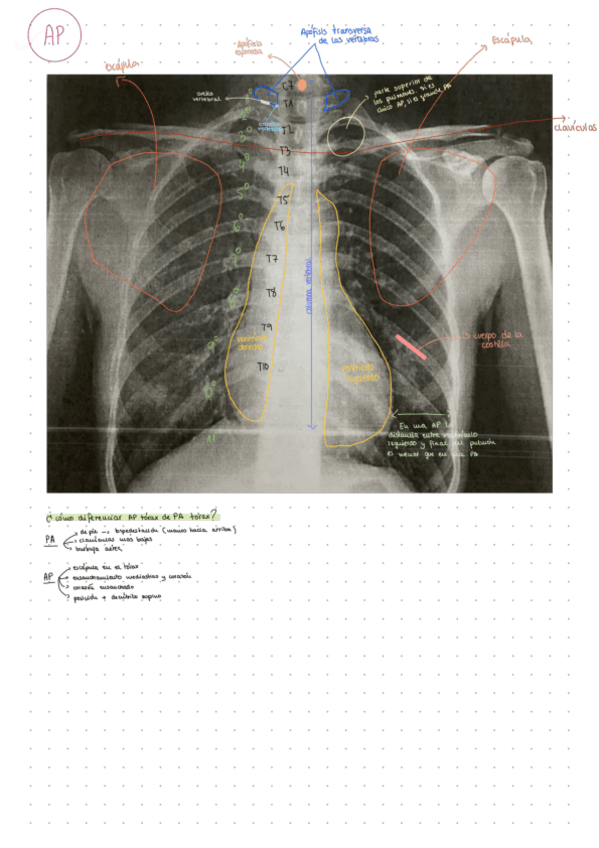

He publicado nuevos apuntes de Anatomía por la imagen: Radiografia-Torax-AP.pdf

1 página